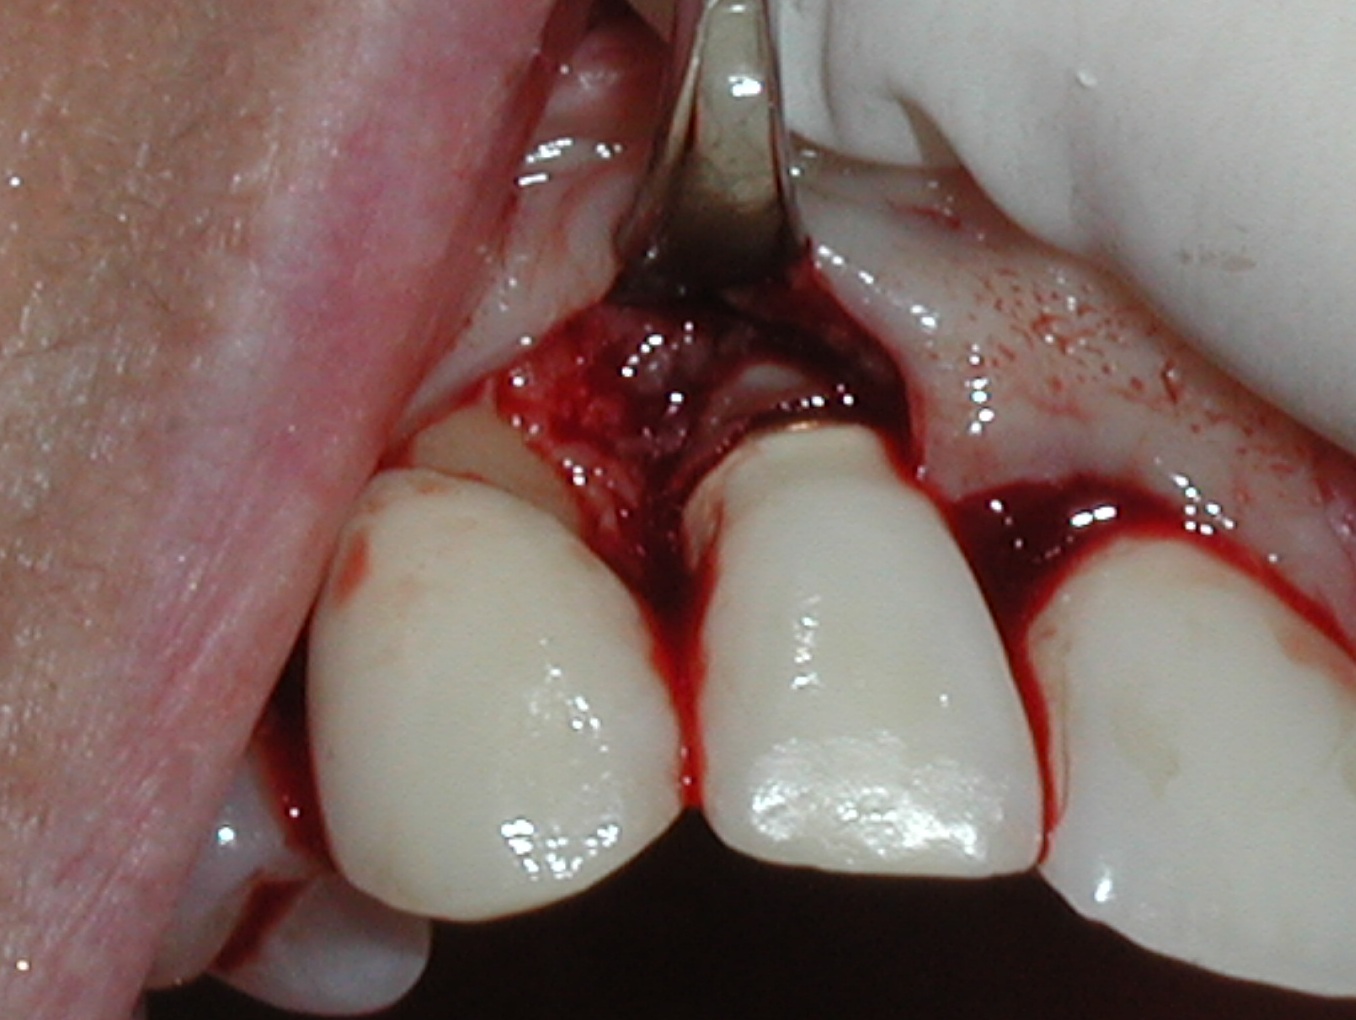

Fig 2. Removal of cement and detoxification with tetracycline hydrochloride.

Figure 2

Fig 3. A freeze-dried bone allograft was placed.

Figure 3

Fig 4. A resorbable collagen barrier was placed.

Figure 4